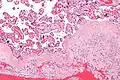

Acute choriodeciduitis, with neutrophils seen in the chorion and decidua.